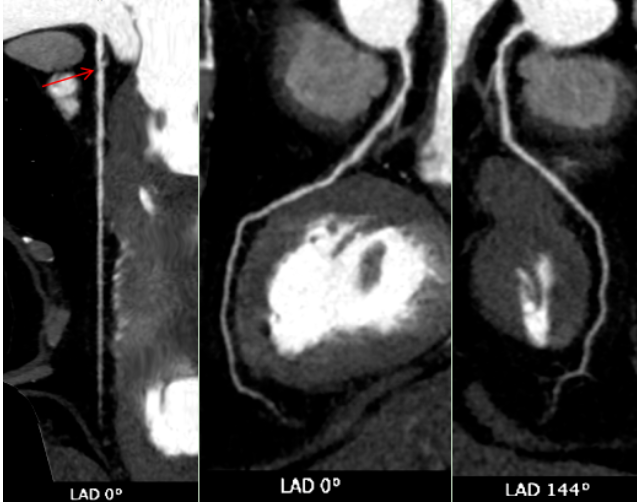

CT表现:冠状动脉粥样硬化,左冠状动脉前降支近端中度狭窄,左冠状动脉前降支心肌桥形成。

冠状动脉CTA已成为筛查和诊断冠状动脉疾病的无创性“金标准”之一。它通过静脉注射对比剂,利用CT快速多层扫描和三维重建技术,直观展示冠状动脉的走行、管腔狭窄程度、斑块性质(如钙化斑块或软斑块)以及血管壁的情况。对于像张老先生这样的病例,CTA不仅能精准测量狭窄百分比,还能识别心肌桥这一解剖变异,评估其与狭窄的相互影响,为临床制定治疗方案(是药物保守治疗,还是需要介入支架或外科搭桥)提供了至关重要的参考。报告中提到的宽体探测器技术,代表了当前CT发展的前沿方向,特别适用于心率快、心律不齐、不能配合屏气或身体虚弱的患者,极大地拓宽了心脏CT检查的适用人群和诊断成功率。